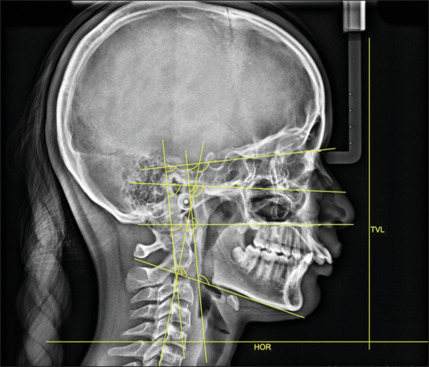

Methodology: A retrospective analysis was undertaken using the pre- and post-treatment records of 35 skeletal class II patients who used the FFRD to achieve class II correction. The metrics suggested by Solow and Rocabado were used to evaluate the cranial and cervical positions. Eleven angular parameters were evaluated to determine the relationship between the mandibular ramus and the skull as well as the upper and middle craniocervical positions. To compare the parameters before and after fixed functional therapy, a Wilcoxon signed rank test was used.

Results: Significant differences were obtained in the parameters SNA, SNB, and ANB post-FFRD. Significant differences were also noted in NL/OPT, NSL/OPT, FH/CVT, FH/OPT, NSL/CVT, NL/CVT, ML/CVT, FH/RL, and oropharynx position.